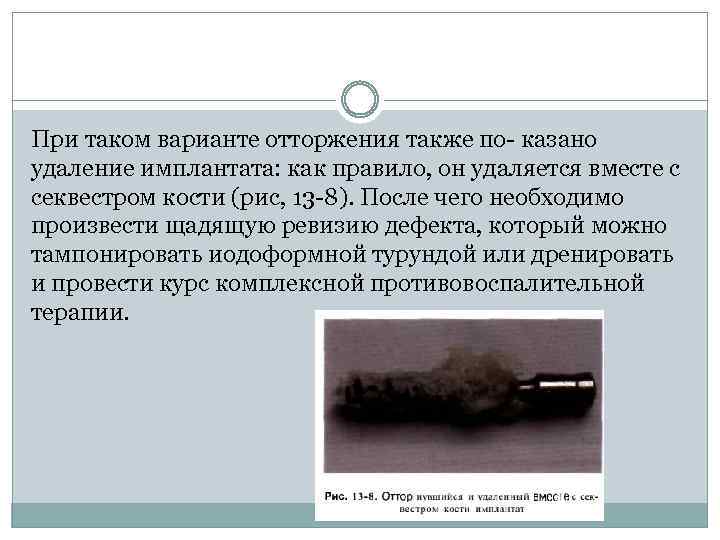

Существуют два варианта отторжения имплан тата, имеющие различную клиническую картину и последствия . Образование секвестра кости, включающе го в себя имплантат. Причинами такого оттор жения могут быть: • значительное нагревание кости во время пре парирования костного ложа имплантата; • остеосклероз участка кости с крайне низким уровнем кровоснабжения. Та кое состояние иногда встречается в области премоляров нижней челюсти при узких альвеолярных отростках.

При таком варианте отторжения также по казано удаление имплантата: как правило, он удаляется вместе с секвестром кости (рис, 13 8). После чего необходимо произвести щадящую ревизию дефекта, который можно тампонировать иодоформной турундой или дренировать и провести курс комплексной противовоспалительной терапии.